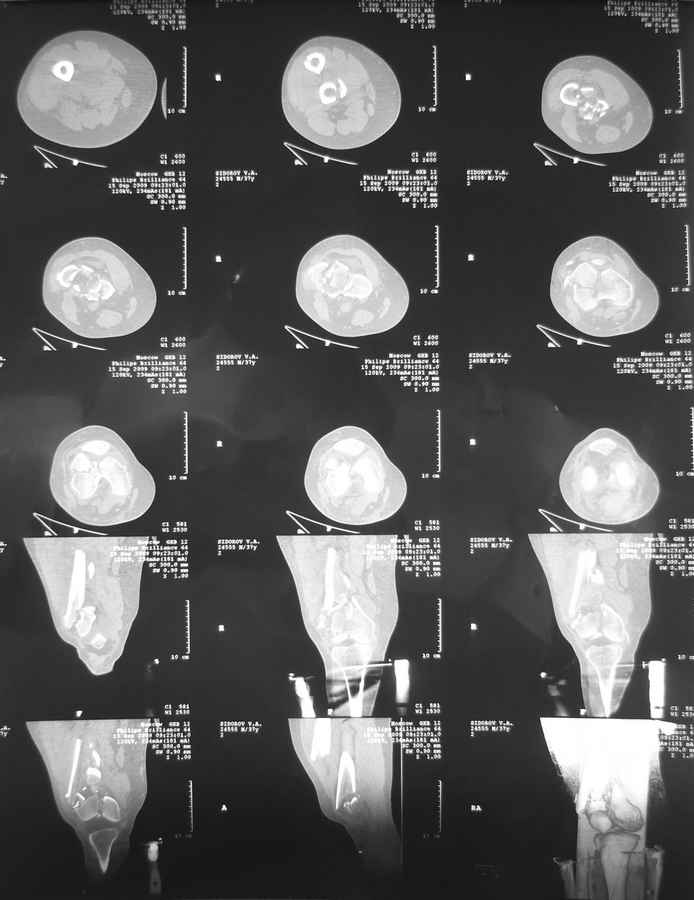

[Ortho] Дистальный перелом бедра

Вообще насчет пластины думали... но если открыться то рассыпится все... LISS можно но тоже тяжело представить...